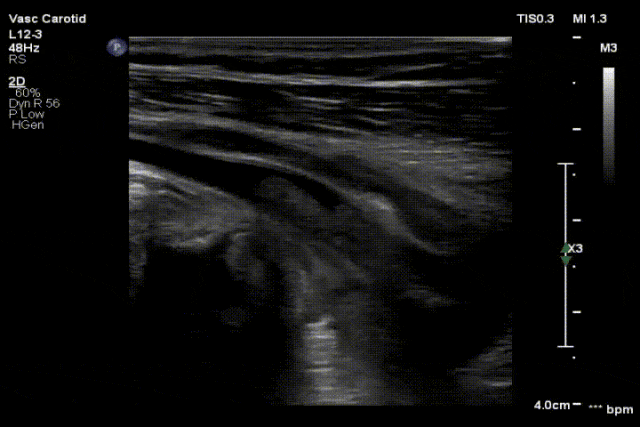

图:a) 穿刺后导丝置入;

图:b) 吸栓装置定位;

图:c) 球囊扩张股浅动脉时球囊远心端显像;

图:d)球囊扩张股浅动脉开口处显像,同时附带血流显像;

图:e)术前评估时腘动脉未见血流图像;

图:f)经吸栓、球囊扩张等治疗措施后腘动脉血流图像